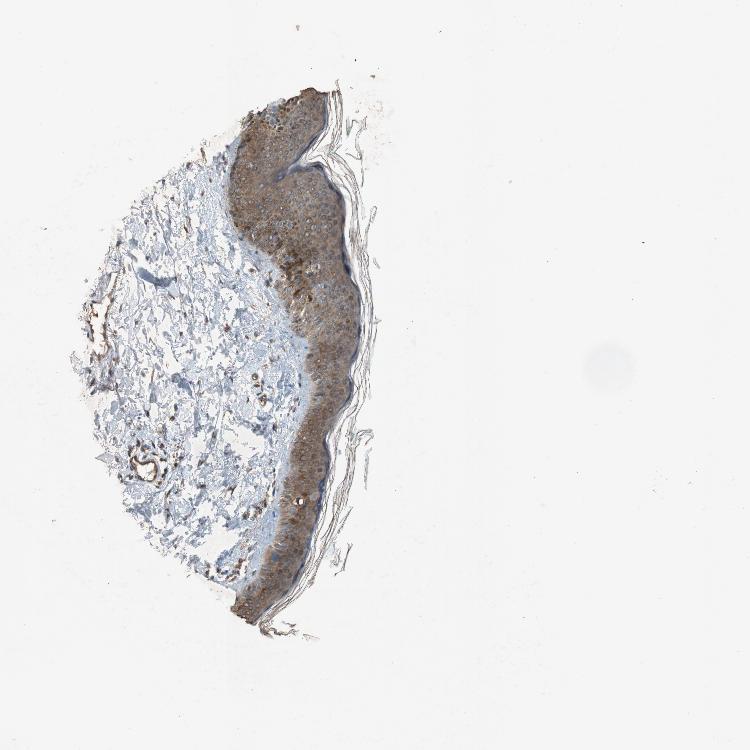

SKIN 1 - Antibody stainingi

Antibody staining in the annotated cell types in the current human tissue is reported as not detected, low, medium, or high, based on conventional immunohistochemistry profiling in selected tissues. This score is based on the combination of the staining intensity and fraction of stained cells.

Each image is clickable and will lead to virtual microscopy that enables deeper exploration of all samples and also displays staining intensity scores, fraction scores and subcellular localization as well as patient and tissue information for each sample.

Antibody HPA035116Antibody CAB010207

Langerhans -Medium

Arrector pili muscle cells Medium-

Cells in basal layer High-

Cells in corneal layer Not detected-

Cells in granular layer High-

Cells in spinous layer High-

Eccrine glands High-

Endothelial cells High-

Extracellular matrix Not detected-

Fibroblasts -Medium

Fibrohistiocytic cells High-

Hair follicles High-

Keratinocytes -Medium

Langerhans cells High-

Lymphocytes High-

Melanocytes HighMedium

Sebaceous glands High-

Vascular mural cells High-